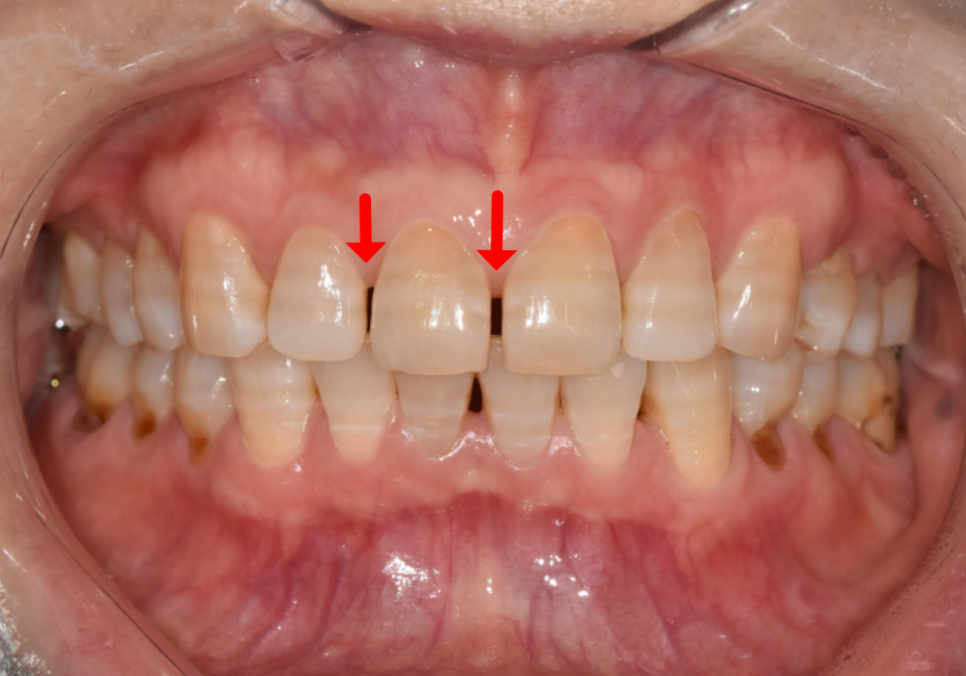

치아가 원래 작은 경우(왜소치)

앞니 사이가 많이 벌어진 경우

왜소치인 경우

치아 사이 공간이 넓은 경우

치아가 작거나 앞니 사이에 여유 공간이 있는 경우에는 치아를 많이 깎지 않아도 됩니다.

231017(전) 231116 (후)